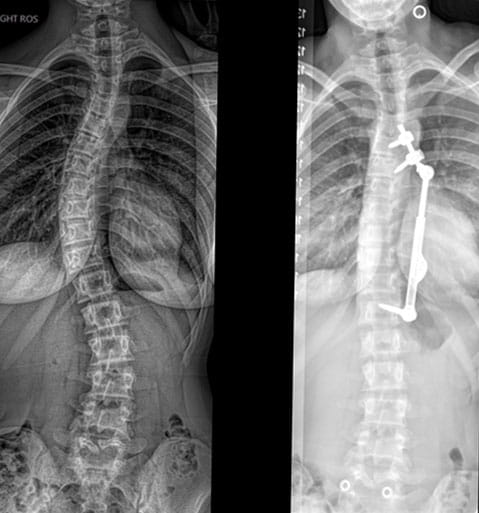

An innovative surgical procedure is expanding treatment options for select patients with adolescent idiopathic scoliosis (AIS). This August, University Hospitals Rainbow Babies & Children’s Hospital became the second site in Ohio and one of about 20 nationally to offer ApiFix®, a less-invasive alternative to spinal fusion that preserves motion and function.

Utilizing a posterior approach, surgeons perform a lateral midline incision to expose the spine and place three pedicle screws into anchor points along the concave side of the curve. Next, a rod is attached and tightened onto the screws. Polyaxial joints enable the device to offer 40 degrees of spherical range of motion. Toward the end of the procedure, an instrument is introduced to elongate the rod and achieve curve correction.

The unidirectional, self-extending rod passively accommodates patient growth over time. Typical length of surgery is 90 minutes to two hours, as compared to four hours for a routine idiopathic fusion. Patients return home in one to two days and resume normal activities in four to six weeks, compared to four to six months of postoperative restrictions with traditional spinal fusion.

"One of the benefits of the ApiFix procedure is that it corrects the curve and holds the spine in a straighter position, but still offers two areas of mobility within the device itself,” says Christina Hardesty, MD, Pediatric Orthopaedic Surgeon at UH Rainbow Babies & Children’s Hospital. “The goal is to leave the spine so well straightened that there isn’t a need for additional correction, but you may gain a few more millimeters.”

Dr. Hardesty and Dr. Glotzbecker first performed the novel procedure on an 18-year-old female. “She met the threshold for surgery but wanted to remain mobile,” Dr. Hardesty says. “She was interested in a procedure that didn’t definitively fuse her thoracic spine.” Now back at school, the patient was able to return home the day after surgery and is doing well. Additional patients are scheduled for the procedure in the coming weeks.